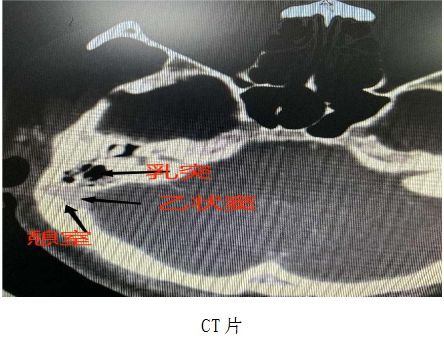

为寻求进一步诊治,患者于是来到达州市中西医结合医院(达州市二医院)耳鼻咽喉头颈外科耳聋、耳鸣及眩晕门诊,经吴映儒副主任医师详细问诊,判断为搏动性耳鸣。在完善听力学和颅脑血管影像学检查,通过颅脑CTA、CTV检查,精准定位责任血管,揪出了导致患者搏动性耳鸣的“元凶”——乙状窦憩室。

乙状窦是颅内重要的静脉结构,位于耳后颅骨内。正常情况下,乙状窦和耳朵之间有一层厚实的乳突骨,就像一堵“隔音墙”。但是,当“隔音墙”有缺损时,血管壁局部在缺损的地方会像吹气球一样鼓起一个小包,这个小包和缺损的骨质就叫憩室,血液流经这个异常的结构就会产生漩涡和湍流,发出比平时更响的“哗哗”声,导致搏动性耳鸣。

经过术前会诊评估和充分沟通,耳鼻咽星空体育官方入口 星空体育官网喉头颈外科吴映儒副主任医师团队决定为患者进行微创显微手术治疗。由于需要紧贴着颅内大血管操作,手术出血风险高。术中,专家团队精细操作,对突出的乙状窦憩室进行缩窄,并同步修补乙状窦骨壁。术后,困扰患者多年的耳鸣消失,听力无影响。目前,患者已经康复出院。